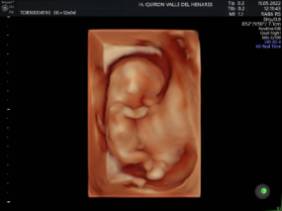

El Hospital Quirónsalud Valle del Henares incorpora un nuevo ecógrafo con tecnología 5 D

El Hospital Quirónsalud Valle del Henares ofrece la posibilidad de realizar ecografías gestacionales 5D. Este tipo de exploración permite obtener una imagen muy realista del bebé y se puede realizar en cualquier etapa de la gestación -aunque lo recomendado es realizarla entre las semanas 28 y 32 de gestación, ya que técnicamente es el mejor momento y es mucho más probable obtener imágenes de buena calidad-.

Al final de la prueba, se entrega a la familia un informe de la ecografía y un soporte digital que contiene las imágenes y los vídeos realizados. Las ecografías 4D y 5D son también llamadas emocionales por la explosión de sensaciones que genera cuando la madre ve por primera vez la imagen del bebé que espera.